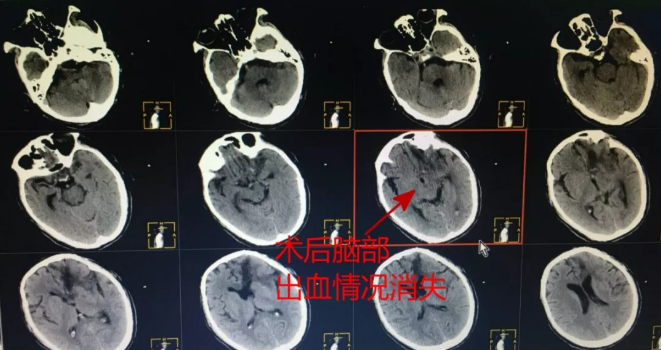

安医大附属阜阳医院神经外科医生李顺利接诊后立即安排王先生进行检查,发现王先生脑内大量出血,血肿严重,考虑存在脑血管畸形的可能性,一小时后,神经外科王少华主任带领团队对王先生紧急实施手术。开颅后,发现王先生脑血管异常杂乱,已经严重畸形,情况十分复杂,但手术团队绝不放弃任何一丝生还的希望,争分夺秒地为王先生实施了“脑内血肿清除+脑血管畸形切除术”。

术前CT,王先生脑内大量出血,血肿严重

术后CT,王先生脑部出血情况消失

正常人的脑血管呈树枝状分叉,而血管畸形就像是“一团乱麻”,乱团的一大特征就是“剪不断、理还乱”,对付这样一个盘根错节的畸形血管团,既要做到全部切除,又不能损伤脑组织,任何一个环节的纰漏都会发生大出血和脑肿胀导致无法挽留的后果。经过5小时的鏖战,神经外科团队成功切除了王先生的畸形血管团和血肿,术后的病理报告也显示出王先生就是由于平常没控制好血压,吸烟不节制而导致脑血管畸形破裂出血。